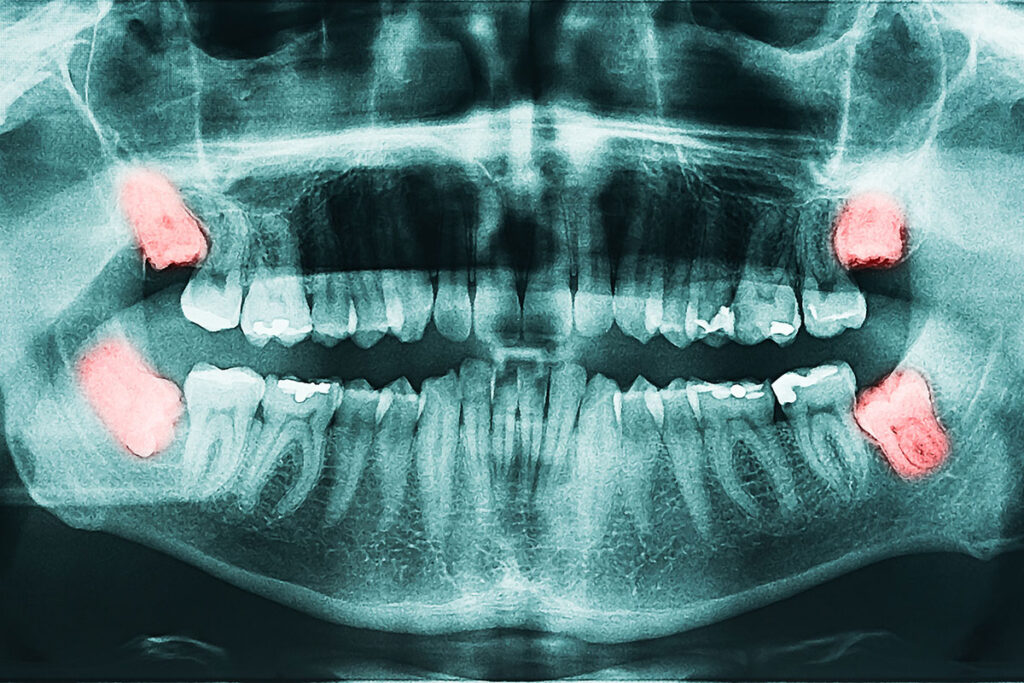

Gömülü diş, sürme zamanı geldiği halde çene kemiği içinde, diş eti altında veya yarı sürmüş şekilde kalan diştir. En sık gömülü kalan dişler 20 yaş dişleri olmakla birlikte, köpek dişleri ve bazı küçük azı dişleri de gömülü kalabilir.

The wisdom teeth are the last molars to appear in the mouth, usually between the ages of 17 and 25. They are also known medically as "third molars". As the jaw structure shrinks, the eruption of these teeth can cause problems for many people. While sometimes they take their place in the mouth without any problems, sometimes they remain embedded or come out crooked. This situation negatively affects dental health.